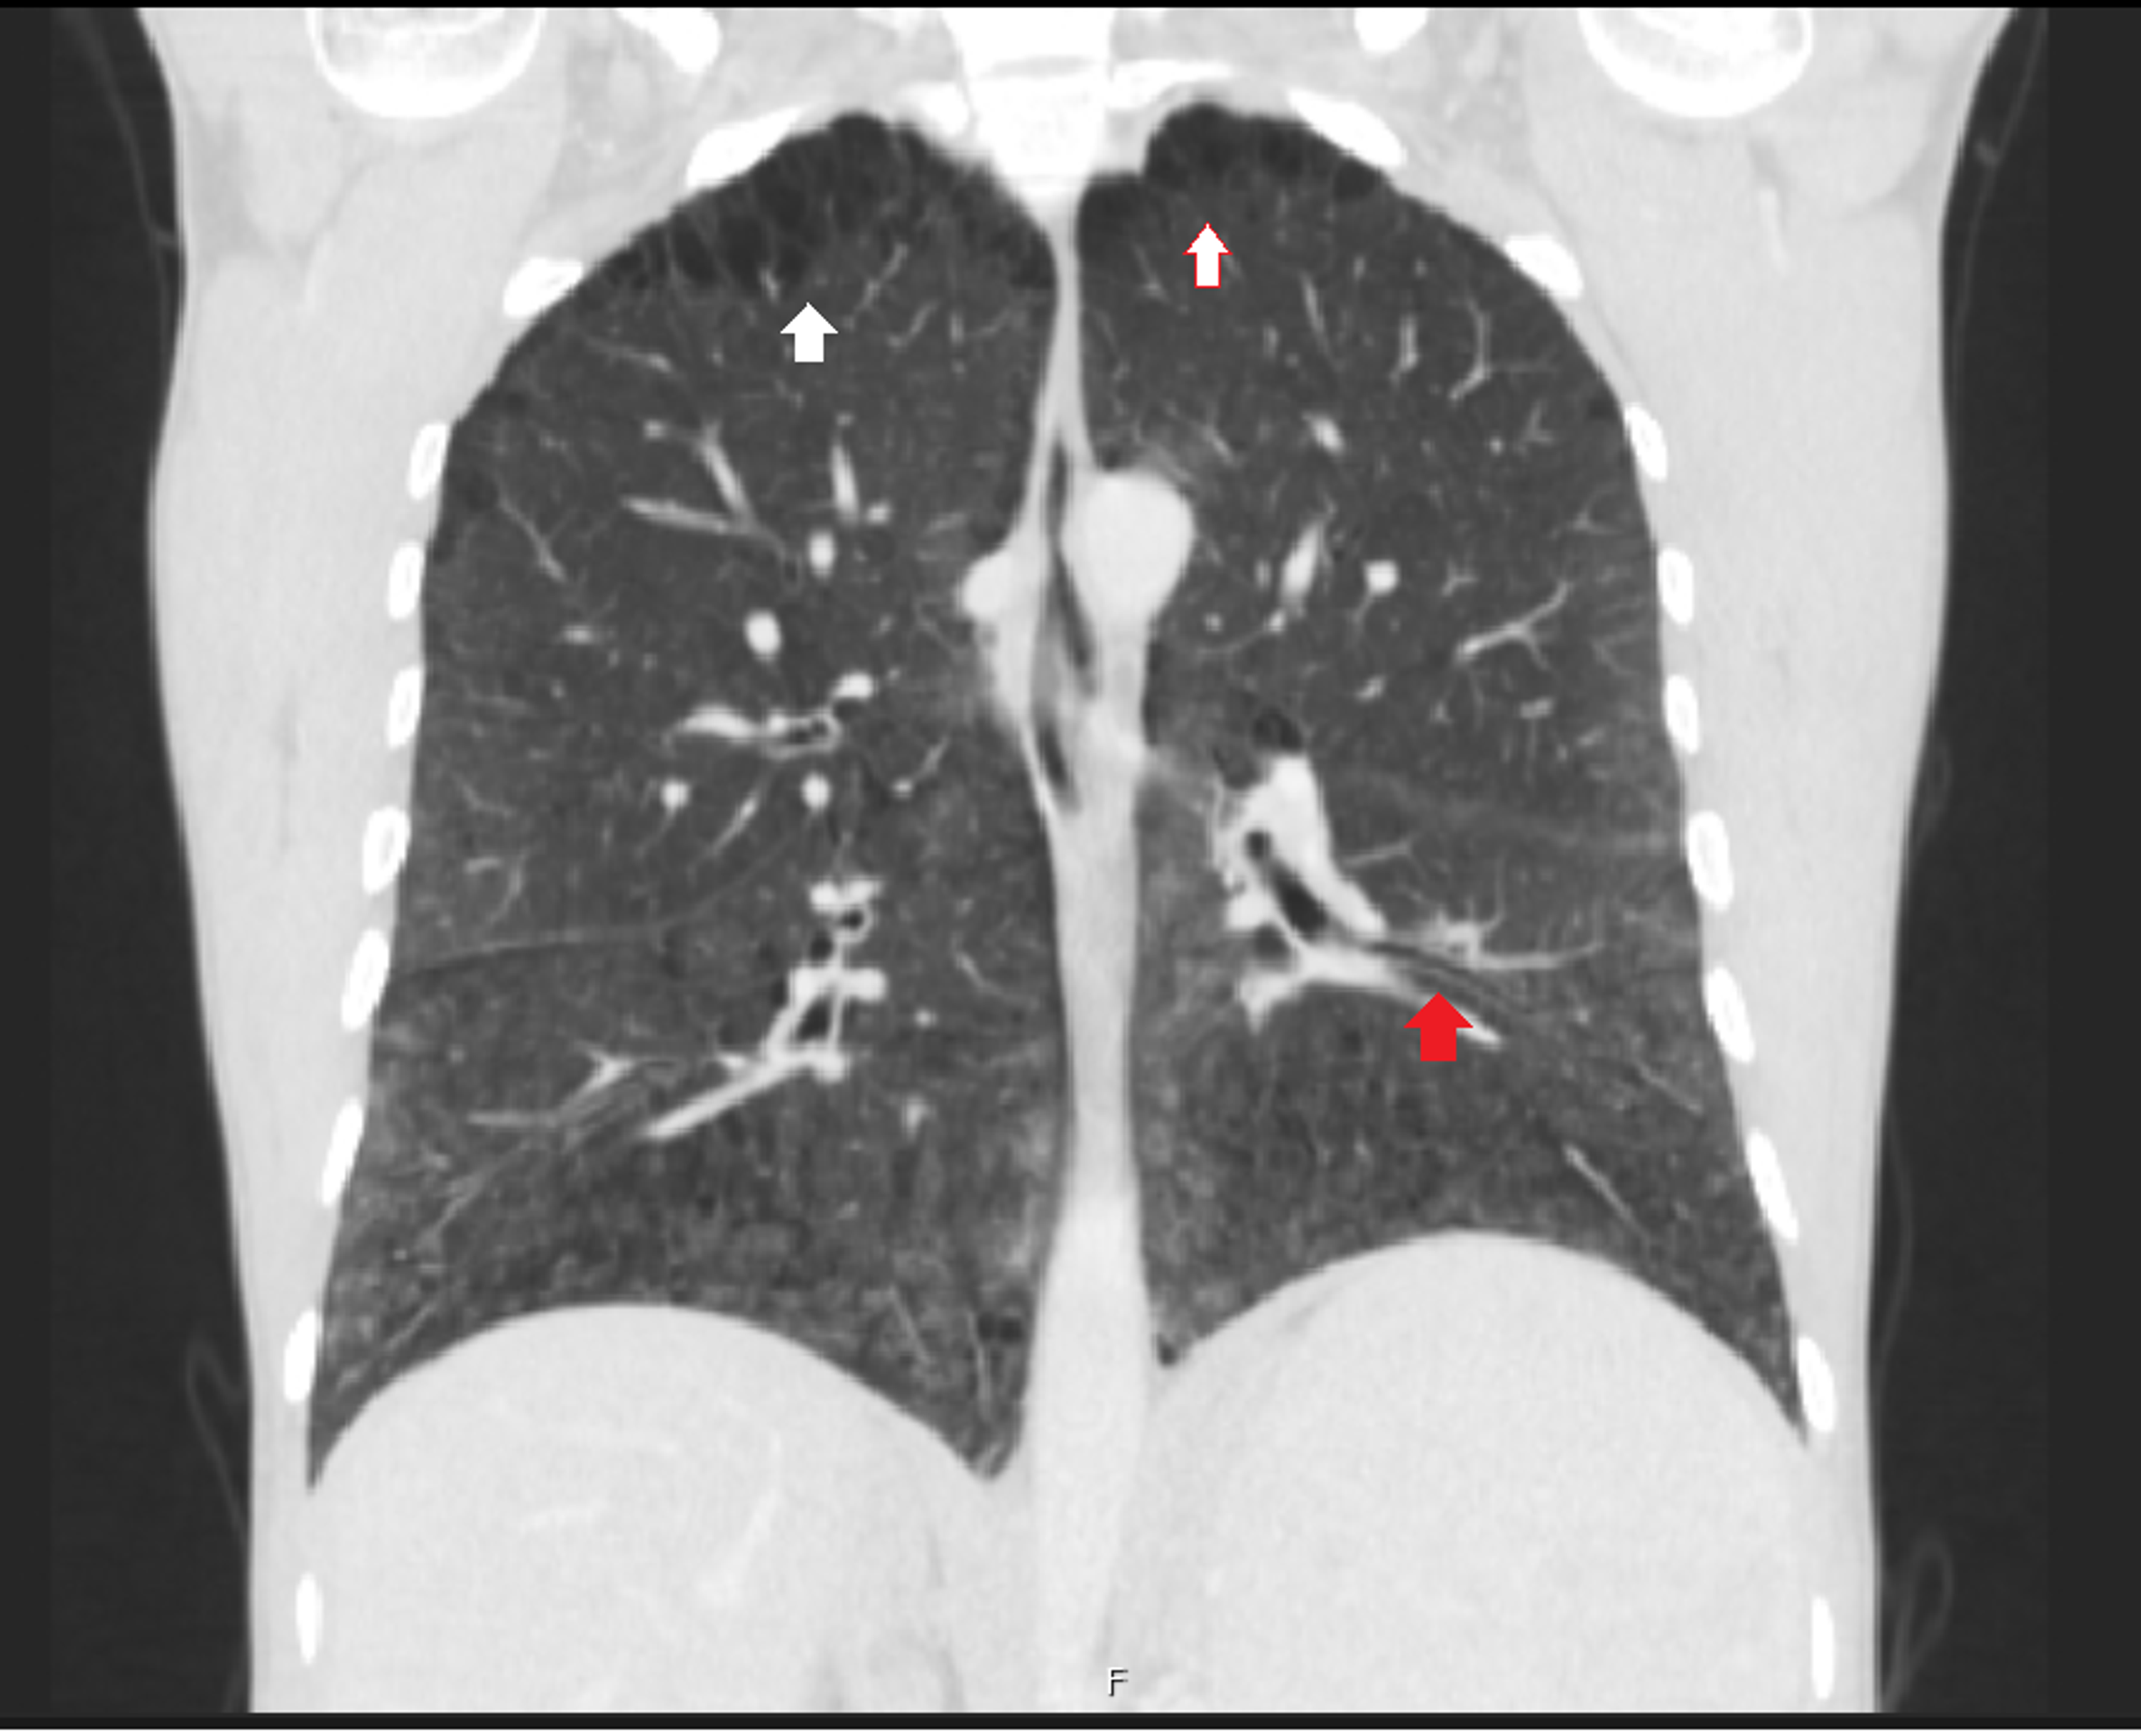

NiemannPick disease type B pulmonary findings (Radiopaedia 43712 Niemann Pick Disease Lung These individuals experience ataxia, dysphonia, dysphagia, liver and lung disease and supranuclear gaze palsy (sngp). This activity reviews the etiology, epidemiology, and. Niemann Pick Disease Lung.

NiemannPick disease type B pulmonary findings (Radiopaedia 43712 Niemann Pick Disease Lung This activity reviews the etiology, epidemiology, and. These individuals experience ataxia, dysphonia, dysphagia, liver and lung disease and supranuclear gaze palsy (sngp). Niemann Pick Disease Lung.